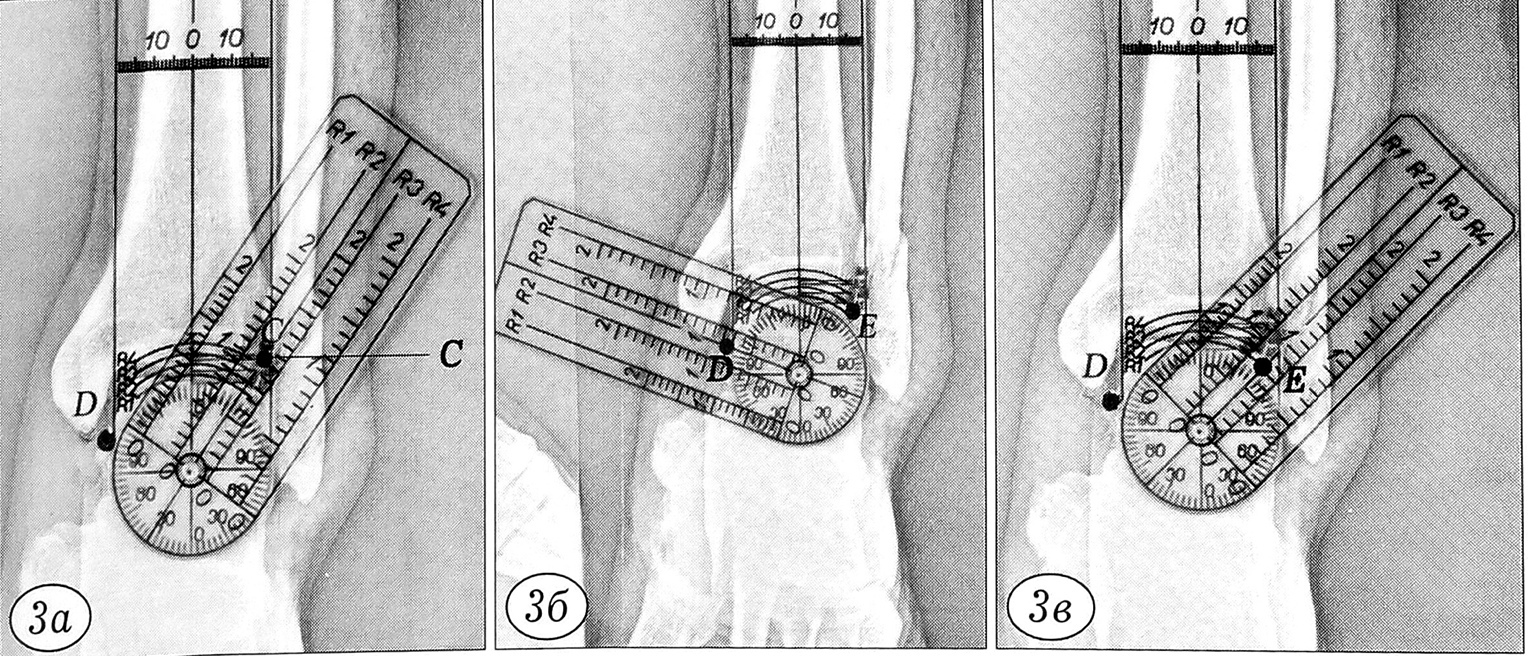

Рис. 3. Определение с помощью измерительного устройства на прямой рентгенограмме левого голеностопного сустава больного Ц. координат точки С (а), точки D (б) и точки Е (в).

Больной Ц., 51 года, поступил в экстренном порядке с диагнозом: закрытый перелом наружной лодыжки слева, подвывих стопы кнаружи. Сделаны рентгенограммы левого голеностопного сустава в прямой и боковой проекциях (рис. 2). Выбраны и обозначены на прямой рентгенограмме следующие рентгенометрические параметры (точки): С — точка сопряжения суставной поверхности большеберцовой кости и наружной лодыжки (характеризует степень повреждения дистального межберцового синдесмоза); D — точка суставной поверхности таранной кости, расположенная на линии, соединяющей центр сустава (центр шарнира) с нижней точкой внутренней лодыжки (характеризует степень подвывиха стопы); Е — точка сопряжения суставной поверхности таранной кости и наружной лодыжки (характеризует степень смещения наружной лодыжки) (см. рис. 2). Описанным выше способом на рентгенограмму голеностопного сустава наложено измерительное устройство (выбран радиус R2), определены полярные координаты точек С, D, Е. Для левого (поврежденного) сустава координаты оказались следующими: точка С (рис. 3, а): осС = 35°, рС = 1,1; точка D (рис. 3, б): ocD = 70°, pD = 0,9; точка Е (рис. 3, в): <хЕ = 45°, рЕ = 0,8.